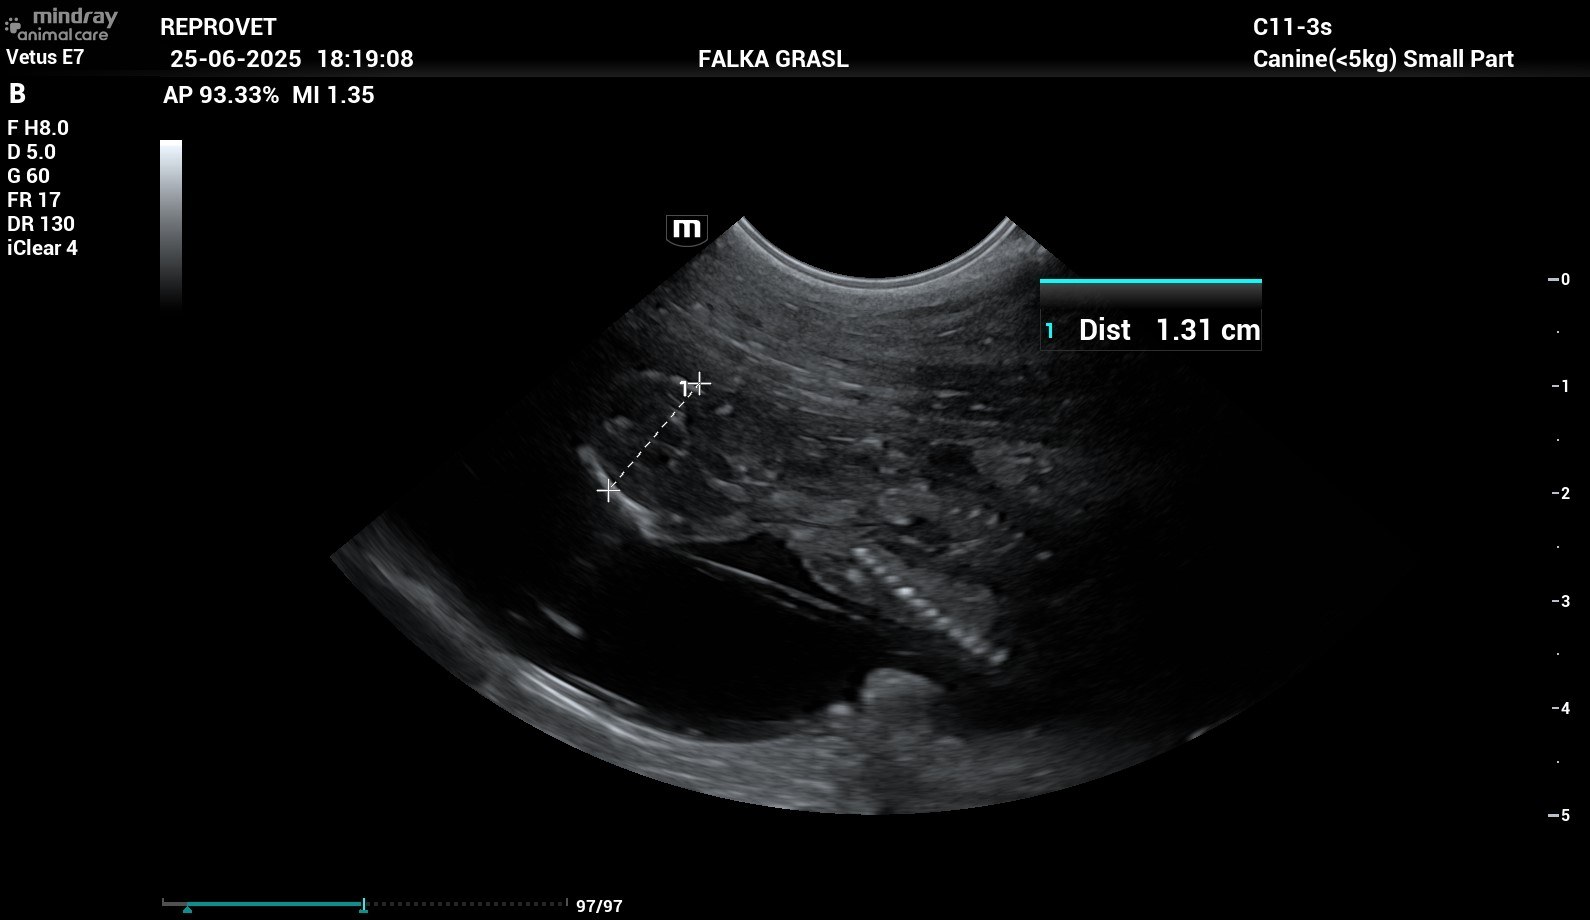

Tag 39 nach dem Eisprung - und alles ist okay!

Falka hat heute wieder Kontrolltermin, Dieter und sie fahren bei einer Affenhitze zur Tierärztin, aber es muss sein. Denn wir wollen, dass Falkas Trächtigkeit für die Welpen und die Mutterhündin gut verläuft und es gibt uns als "Erstlings-Züchter" das Gefühl, nichts zu übersehen, wenn man engmaschige Untersuchungen durchführen lässt. Auf jeden Fall ist es so, dass alles bestens ist: Die Kleinen gedeihen prächtig, sie sind jetzt in etwa 6 cm lang, Falkas Bauchumfang ist auch schon um 8 cm gewachsen, die Embryonen bewegen sich heftig in Falkas Bauch sagt Dieter.